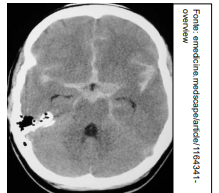

Um médico está atendendo Laura, estudante que retorna às aulas após internação recente em UTI por acidente vascular cerebral (AVC). No relatório de alta, consta que ela apresentou AVC tipo Hemorragia Subaracnoide Aneurismática, e há uma cópia da tomografia computadorizada de crânio, sem contraste, realizada pela paciente na admissão. A imagem que melhor corresponde ao achado do exame de imagem de Laura é: